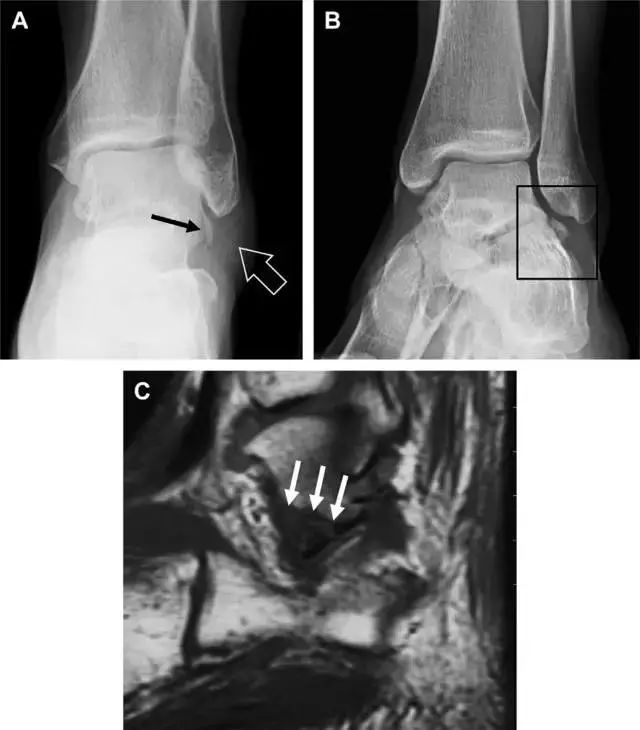

距骨外侧突骨折

距骨外侧突骨折常因踝外翻背屈时,跟骨上外侧面撞击距骨外侧突下缘导致,或偶尔由踝内翻引起,被称为「滑雪板者骨折」。这种骨折只能在踝关节正位片上发现,而且外踝远端表面软组织肿胀往往是一个重要线索(图 4)。

图 4 距骨外侧突骨折。A 正位片示内翻损伤所致的距骨外侧突撕脱性骨折(箭头);B 另一位患者,踝外翻损伤导致典型的「滑雪板者骨折」,X 片上可见一较大的三角形骨折块(方框);C 第二位患者的 MRI 矢状位 T1 加权像示横行骨折(箭头)。

19

距骨后突骨折

距骨后突有内侧结节和外侧结节,距骨后突内侧结节撕脱性骨折常发生在背屈内旋的*力暴**作用下。严重跖屈时,胫骨后缘和跟骨挤压距骨后突外侧结节呈楔形,易发生粉碎性骨折。这些骨折细微且需与三角骨鉴别。侧位片观察距骨后突骨折最佳,常规拍片很难发现,当高度怀疑这种骨折又没法做 CT 时,建议加做多个角度的外旋斜位片(图 5)。

图 5 距骨后突骨折。侧位片(A)和 MRI 矢状位 T1 加权像(B)均示后外侧突的简单骨折(箭头),再次阅片时才发现 X 线片上的骨折;侧位片(C)和 CT 横断面图像示后内侧突的粉碎型骨折(箭头)。